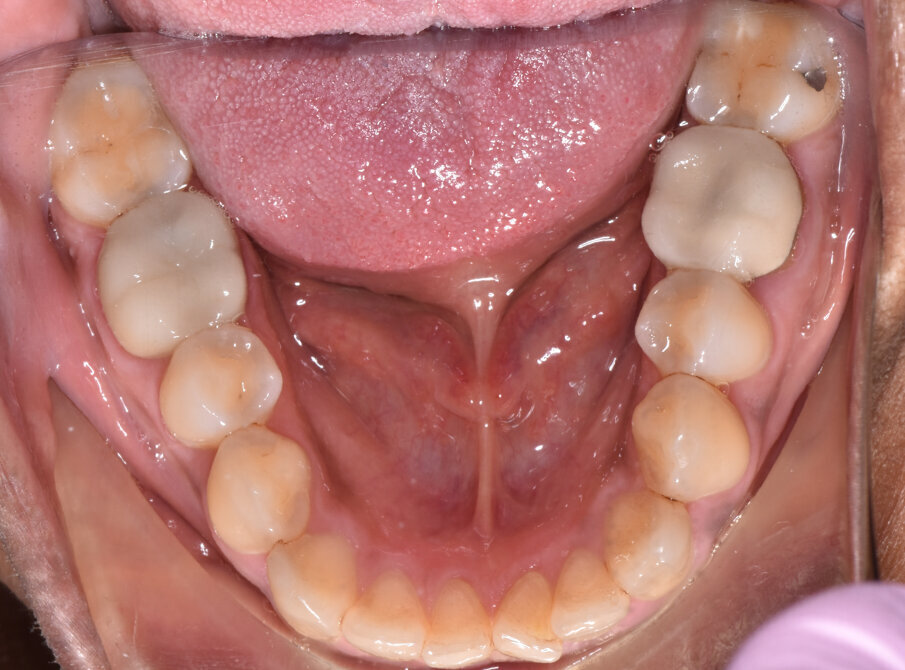

A 56-year-old female patient presented with a Class III malocclusion, anterior crowding and a 2-3 mm anterior open bite. Clinical photographs showed an ideal incisor display upon smiling. The panoramic film was unremarkable, and the lateral cephalometric film revealed a negative 1 mm overjet. (Figs. 1 to 10)

Lower arch expansion and interproximal reduction of 0.5 mm were prescribed on all of the lower incisors from mesial of canine to mesial of canine before the 19th aligner. (Fig. 13) IPR would allow retraction to assist the Class III elastic correction of the negative overjet. Additionally, since counterclockwise autorotation of the mandible would project the lower incisors anteriorly, retraction would also assist in mitigating this effect.

Retraction and uprighting of the lower incisors would also achieve relative extrusion, further assisting in the closure of the anterior open bite. (Figs. 14,15)